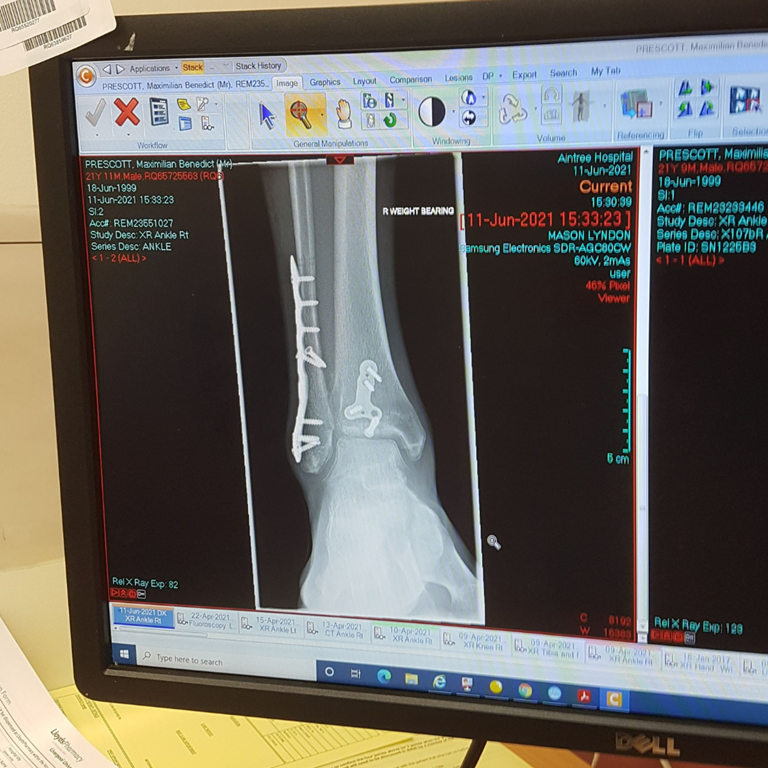

I broke two bones in my ankle and ruptured my deltoid ligament, meaning it was an unstable ankle fracture and would require surgery (see Picture 2). I was told it would be a good outcome if I could walk again without pain. The first two weeks were all about managing pain, resting, and keeping the ankle elevated to reduce the swelling for the surgery. After the surgery, the following two weeks were much of the same until the cast could be removed. Essentially, I would spend the whole day in bed only getting up to make food or go to the bathroom.

I was told by the doctors that I might not be able to walk again without pain, which is a possibility I had to come to terms with. However, I knew that I would do everything in my power to ensure the best possible recovery. Four days after the surgery, I began to do what exercise I could. I did my first set of pullups since the accident (I thought my heart was going to beat out of my chest from being so unfit!), and I started doing daily grip strengthening exercises and core workouts. As my confidence grew, I began to do more rigorous workouts, and two weeks after the operation, they removed the cast and stitches.

My God that was a huge relief! I looked at what was once my lower leg, but had become a skinny, stiff, alien-looking object attached at my knee. My calf had wasted away to the extent that my foot looked like it belonged to a hobbit (i.e. disproportionately large and swollen). But at least I could now start doing ankle mobility exercises, which I did four times a day, and gently weight bear in a moon boot. This allowed me to do more complex workouts, and after a week, I felt confident enough to go for my first climb since breaking my ankle.